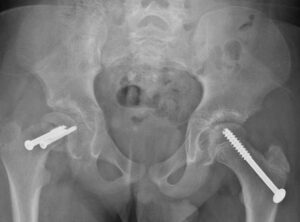

In Situ Fixation in the Opposite Hip

In certain cases, patients with SCFE are at an increased risk of developing the condition in the opposite hip. If your child falls into this higher-risk category, the doctor may recommend preventive treatment by inserting a screw into the unaffected hip during the same surgical procedure. This proactive approach can significantly reduce the likelihood of SCFE occurring in the opposite hip. The doctor will discuss this option with you in detail and determine whether this additional step is appropriate for your child based on their individual risk factors.

In this X-ray, two screws have been inserted in the patient's right hip to stop progression of a slip. A single screw has been inserted in the left hip to prevent SCFE from developing.